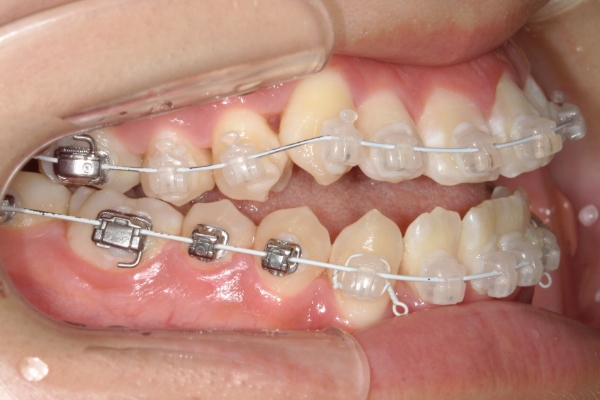

矯正治療

矯正装置を装着し、歯を動かし始めます。通院頻度は装置によって変わりますが、基本的には3~8週間に1回程度です。 1回の治療時間は20〜60分です。

1〜3か月毎にお口の中の写真を撮影し、患者さまへ治療の進行度をお伝えします。写真で歯並びの変化を実感していただくことは、患者さまご自身のモチベーションを保つことにもつながります。

PROCESS

3か月

骨格的に下あごが前下方に長いことが原因で、受け口、開咬(前歯が当たらない)の症状がでていました。また下あごが右にずれており、その影響で上下の歯列正中(真ん中)の大きなずれも生じていました。顎変形症手術も選択肢の一つでしたが、患者さまの希望もあり、下顎左側小臼歯の抜歯をして通常の歯列矯正で治療をしました。

前歯、奥歯の噛み合わせが大きく改善され、上下の歯真ん中が一致しました。食べ物が噛みやすくなったこともですが、歯列の見た目が整った点にも患者さまは満足されていました。